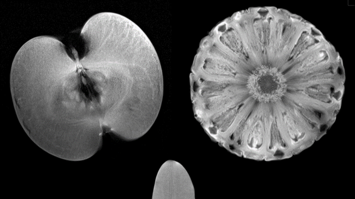

MitmachstationLive-Experiment am 7 Tesla MR ScannerThema: Gesundheit TechnikWie kann man in das Innere von Obst sehen, ohne es aufzuschneiden? Wie kann man ohne Operation einen Blick ins Gehirn werfen? Wieso ist der 7 Tesla MRT Scanner von großem Vorteil? In kurzen live Experimenten als Teil der geführten Tour werden Sie tiefere Einblicke in die Funktionsweise der MRT zu bekommen.Medizinische Forschungsmeile17:00 - 23:00 -

AusstellungMini-Magnet-Resonanz Experimente und Meniskus-Schaden in MR-BildernThema: Gesundheit TechnikBei dieser Doppelstation wird ein kleines Magnetresonanz (MR) Tischgerät gezeigt, mit dem einfache Versuche zur Erläuterung des Funktionsprinzips eines MR-Tomographen demonstriert werden. Ein Bildschirm zeigt MR-Schnittbilder eines menschlichen Knies mit Gewebetypen inkl. einem Meniskusschaden.Medizinische Forschungsmeile17:00 - 23:00 -